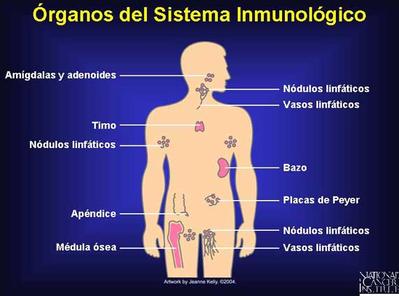

¿Una cura para el COVID-19? La respuesta está al interior de nuestro cuerpo

CIUDAD DE MÉXICO, 16 septiembre 2020/ BLOOMBERG / MICHELLE CORTEZ,EL FINANCIERO/ Los anticuerpos, las proteínas ...